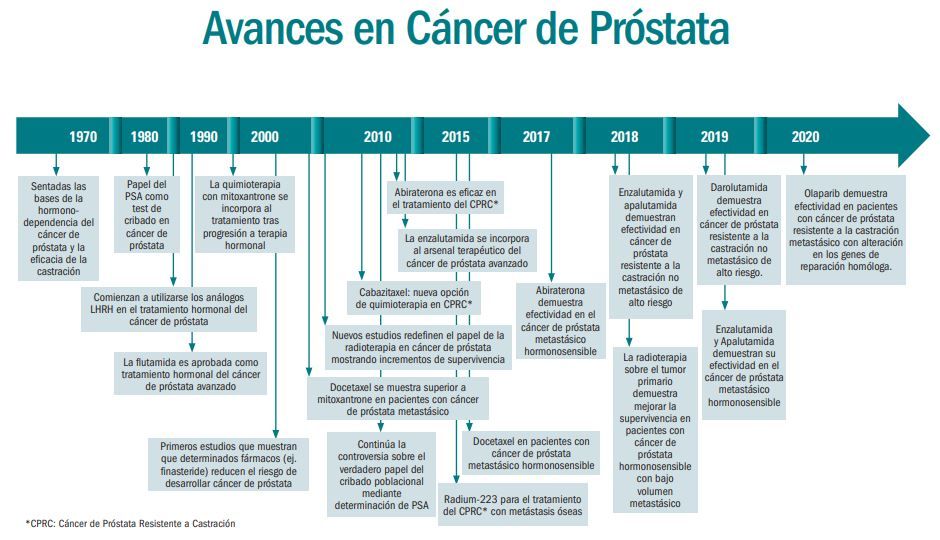

La supervivencia de los pacientes con cáncer de próstata avanzado se ha triplicado en los últimos 15 años gracias al desarrollo de nuevos agentes hormonales, quimioterapia o radiofármacos, pasando de 12-18 meses en 2005, cuando solo se disponía de quimioterapia, a más de los 36 meses actuales. Estos son algunos datos que ha destacado la Sociedad Española de Oncología Médica (SEOM) en el marco de la campaña de comunicación “En Oncología cada AVANCE se escribe en Mayúsculas”, coincidiendo con el Día Mundial del Cáncer de Próstata que se celebra mañana viernes, 11 de junio.

Es en estos casos avanzados (resistencia a la castración y enfermedad hormonosensible metastásica) donde se ha realizado la mayoría de avances en el tratamiento de la enfermedad. Entre los años 2011 y 2014, el desarrollo de nuevos agentes hormonales (abiraterona, enzalutamida), quimioterapia (cabazitaxel) o radiofármacos (Ra-223) ha permitido aumentar la supervivencia desde los 12-18 meses en 2005, cuando sólo estaba disponible la quimioterapia con docetaxel, a los 32-36 meses actuales.